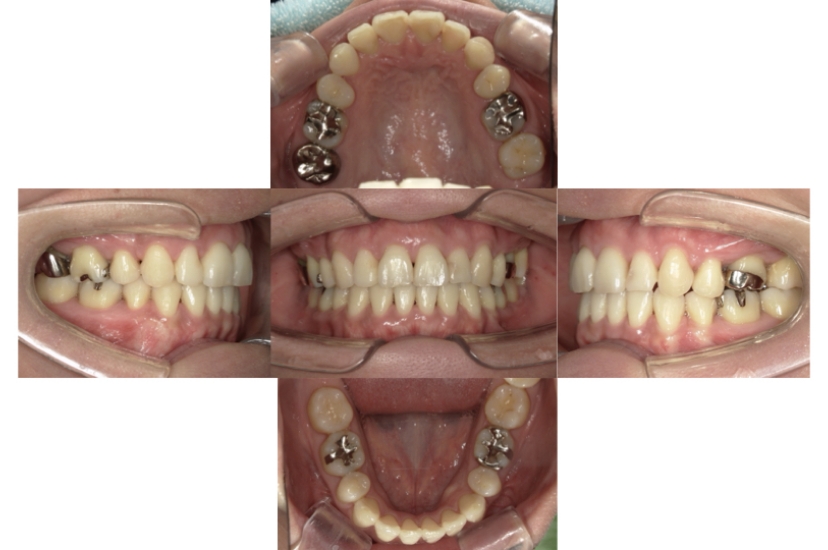

BEFORE

AFTER

上下顎前突、叢生(上下出っ歯、上下の前歯のガタガタ)のケースです。

装置はラビアル(上下表側)で、上下顎の小臼歯を4本抜歯を行っています。抜歯したスペースを使って、上下の前歯の後方移動と叢生(ガタガタ)の改善を行っています。

主訴 前歯のガタガタと口元がでているのが気になる。

年齢・性別 30歳 女性

お住まいの地域 東京都大田区

治療方針 抜歯スペースを利用して上前歯の叢生(ガタガタ)と口元突出の改善

抜歯部位 上下顎左右第一小臼歯

使用装置 ラビアル(上下表側)、顎間ゴム

治療期間 1年11か月

治療回数 13回

リテーナー クリアリテーナー